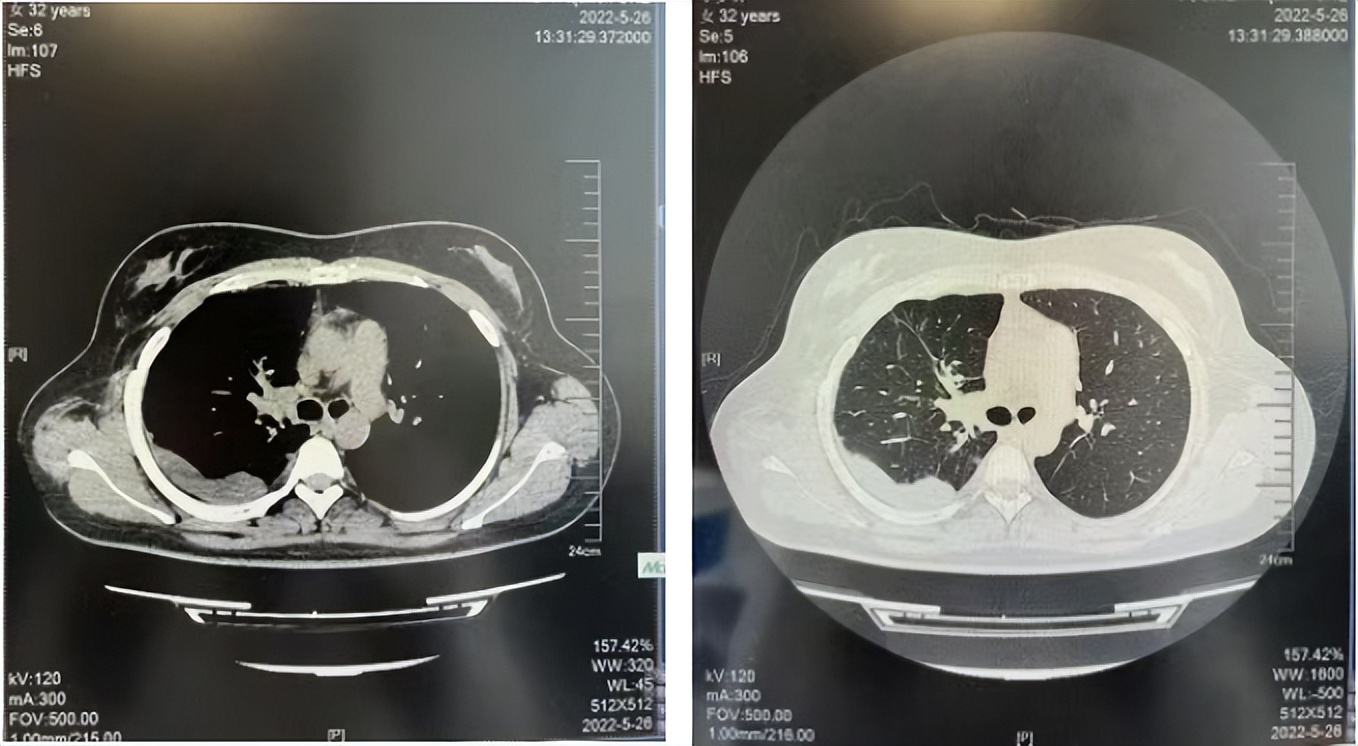

治疗经过:2023年3月27日始行恩沙替尼靶向治疗至今,最佳疗效为PR,末次评效为维持PR。期间出现轻度肝功能异常(DILI 1级),对症处理后好转。截止目前PFS为26个月。

2024年6月复查PR(最佳疗效)

2024年12月复查维持PR

2025年3月复查维持PR